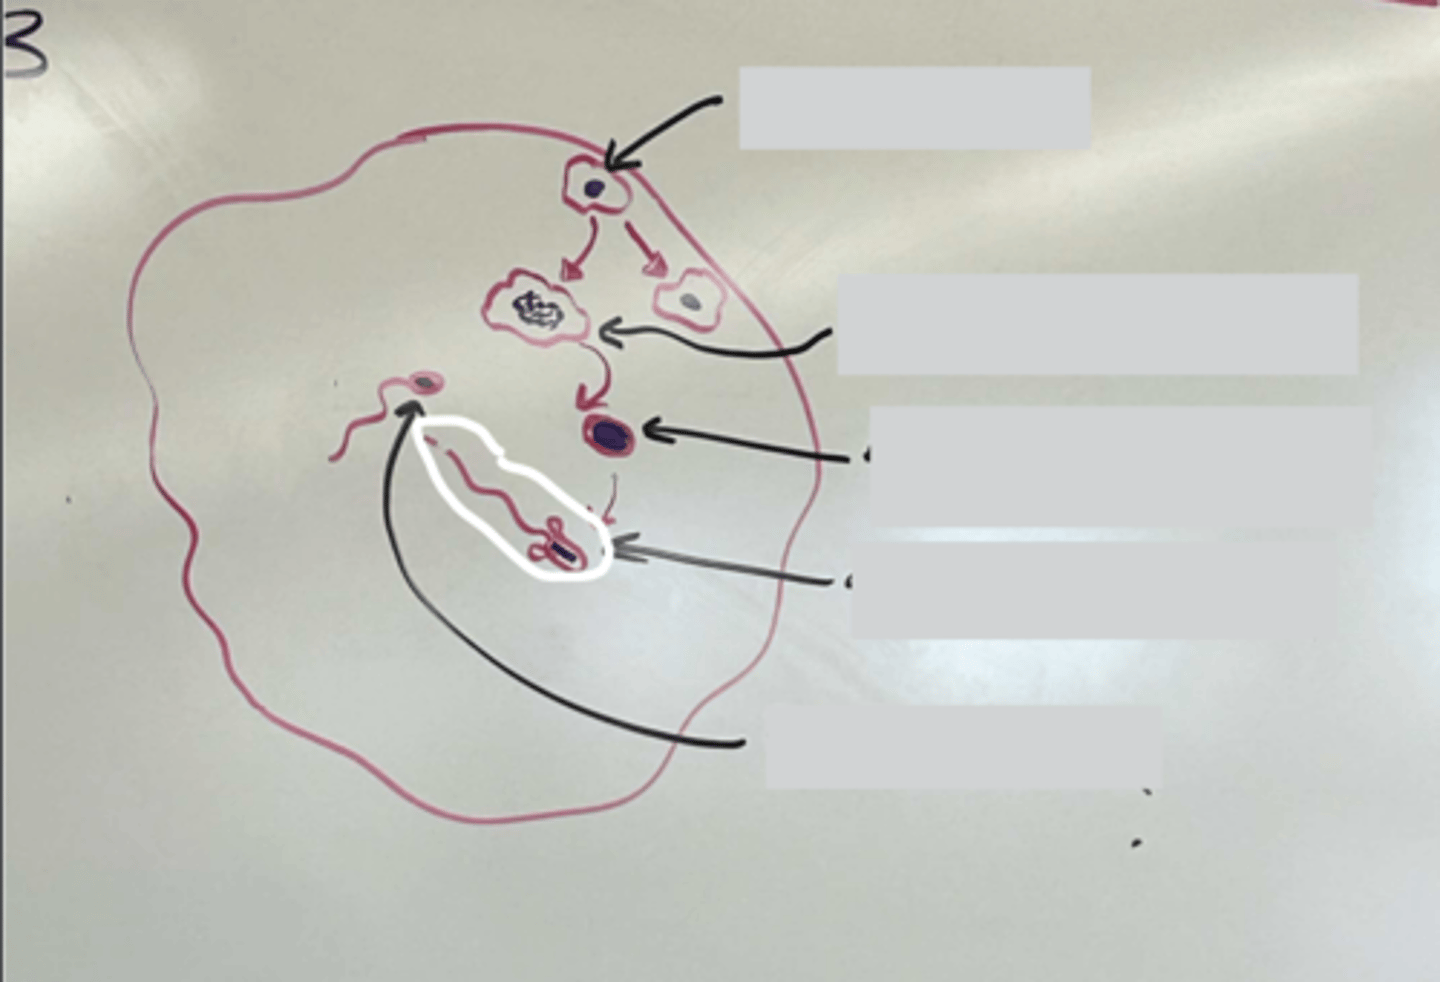

Spermatogenesis

Spermatogenesis

Spermatogonia

Primary spermatocyte

Spermatogonia

Spermatid (early)

Primary spermatocyte

Spermatid (late)

Spermatid (early)

Spermatozoon

Spermatid (late)

Spermatozoa